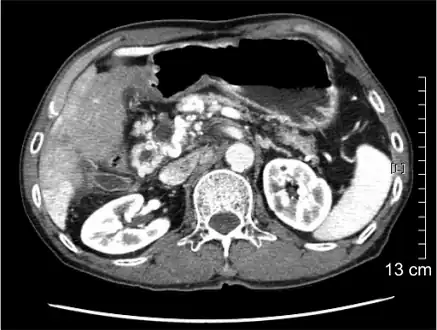

Computed tomography scan showing portal vein thrombosis (with cavernous change of portal vein )

The diagnosis of portal vein thrombosis is usually made with imaging confirming a clot in the portal vein; ultrasound is the least invasive method and the addition of Doppler technique shows a filling defect in blood flow. PVT may be classified as either occlusive or nonocclusive based on evidence of blood flow around the clot.[5] An alternative characterization based on site can be made: Type 1 is limited to the main portal vein, Type 2 involves only a portal vein branch (2a, or 2b if both branches are affected), and Type 3 if clot is found throughout both areas.[8] Determination of condition severity may be derived via computed tomography (CT) with contrast, magnetic resonance imaging (MRI), or MR angiography (MRA). Those with chronic PVT may undergo upper endoscopy (esophagogastroduodenoscopy, EGD) to evaluate the presence of concurrent dilated veins (varices) in the stomach or esophagus.[3] Other than perhaps slightly elevated transaminases, laboratory tests to evaluate liver function are typically normal.[1] D-dimer levels in the blood may be elevated as a result of fibrin breakdown.